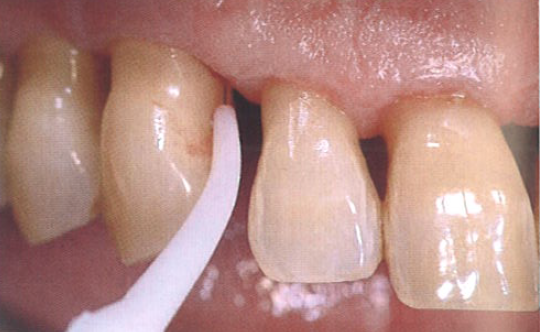

在为期15年的牙周维护治疗期间,由于患者的疏忽偶尔没有按时复诊,就诊时观察到牙周炎症的复发。图1显示探诊深度为7 mm,并伴有探诊出血。

图1  患者的牙周探诊深度为7 mm,且伴有探诊出血